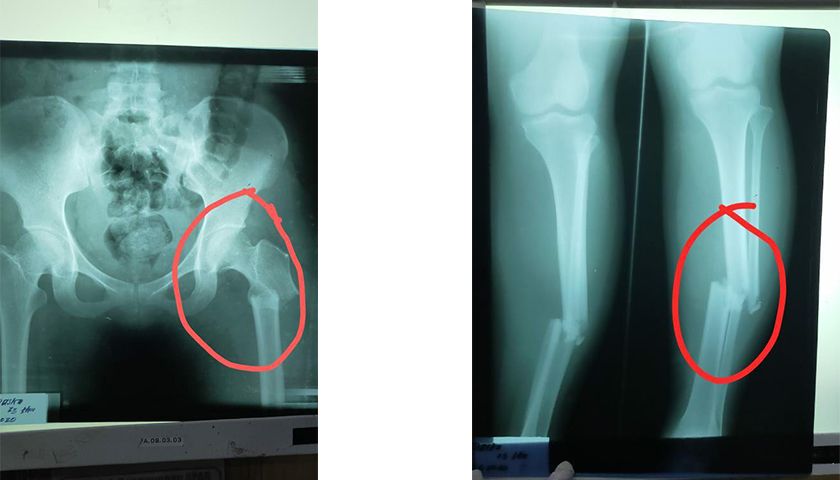

Teman Aisyah tidak mengalami luka parah, berbeda dengan Aisyah yang kondisinya memprihatinkan. Aisyah mengalami patah tulang betis, patah tebu tulang paha, pinggang dan bahu kanannya yang kini sulit digerakkan.

Kemungkinan pengobatan Aisyah akan membutuhkan waktu yang lama dan biaya yang besar. Setelah dilakukan pengobatan dan CT Scan di Rumah Sakit di Kabupaten Pelalawan. Akhirnya Aisyah harus dirujuk ke Rumah Sakit Ibnu Sina Pekanbaru karena luka yang dialami Aisyah cukup parah dan terdapat benda yang masuk ke daging.